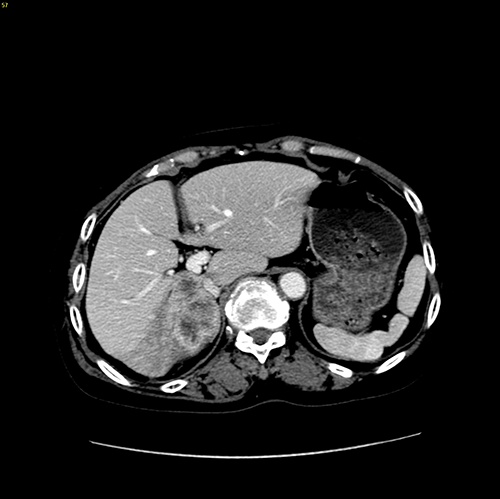

右肝胆管细胞癌-扩大右半肝切除